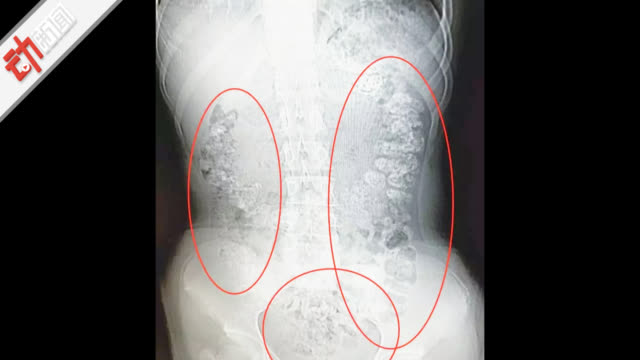

中国新闻周刊:喝奶茶肚疼检查发现胃内百余颗珍珠【14岁女孩喝奶茶肚子疼5天挂急诊胃内发现百余颗“珍珠”】5月28日晚,浙江省诸暨市,14岁女孩小沈(化名)到医院急诊科就医,称肚子疼5天无法排便,吃不下东西。经医生检查,小沈胃肠道布满高密度颗粒状阴影,疑似珍珠奶茶里的“珍珠”,医生粗略估计有百余颗。医生推断,小沈因长期喝珍珠奶茶“珍珠”在体内未消化。新京报动新闻的秒拍视频新京报动新闻